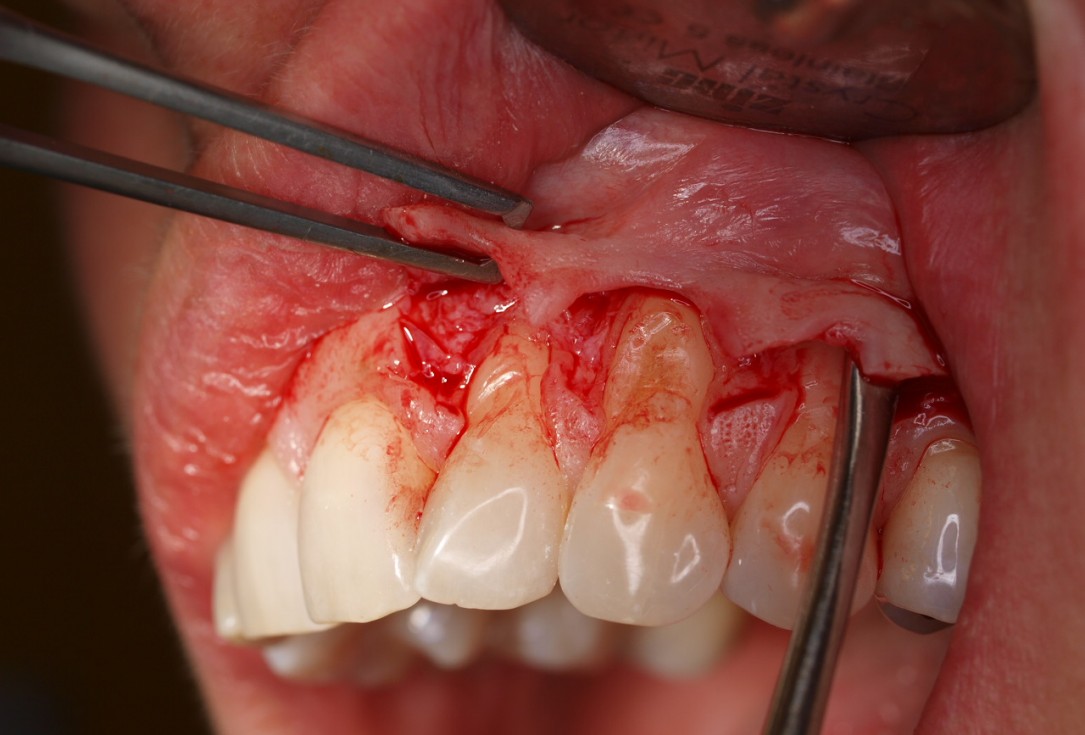

Multiple gingival recessions treated by MCAT with mucoderm® and Straumann® Emdogain® (2) - Rathe

Pre-operative clinical situation. Shallow multiple adjacent gingival recessions in the first quadrant.